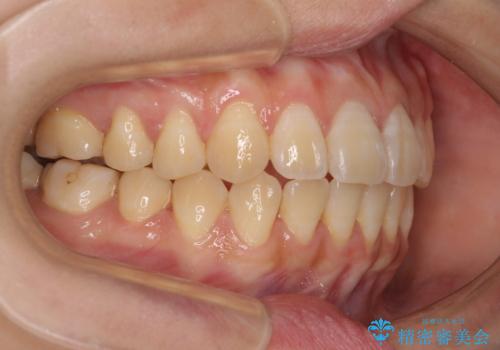

舌の突出癖による開咬と前歯の突出 インビザライン矯正治療

- 上下前歯の非接触と叢生を気にして来院された患者様です。

開咬の改善はインビザラインの最も得意とするところであるため、インビザラインを用いて矯正治療を行うこととしました。